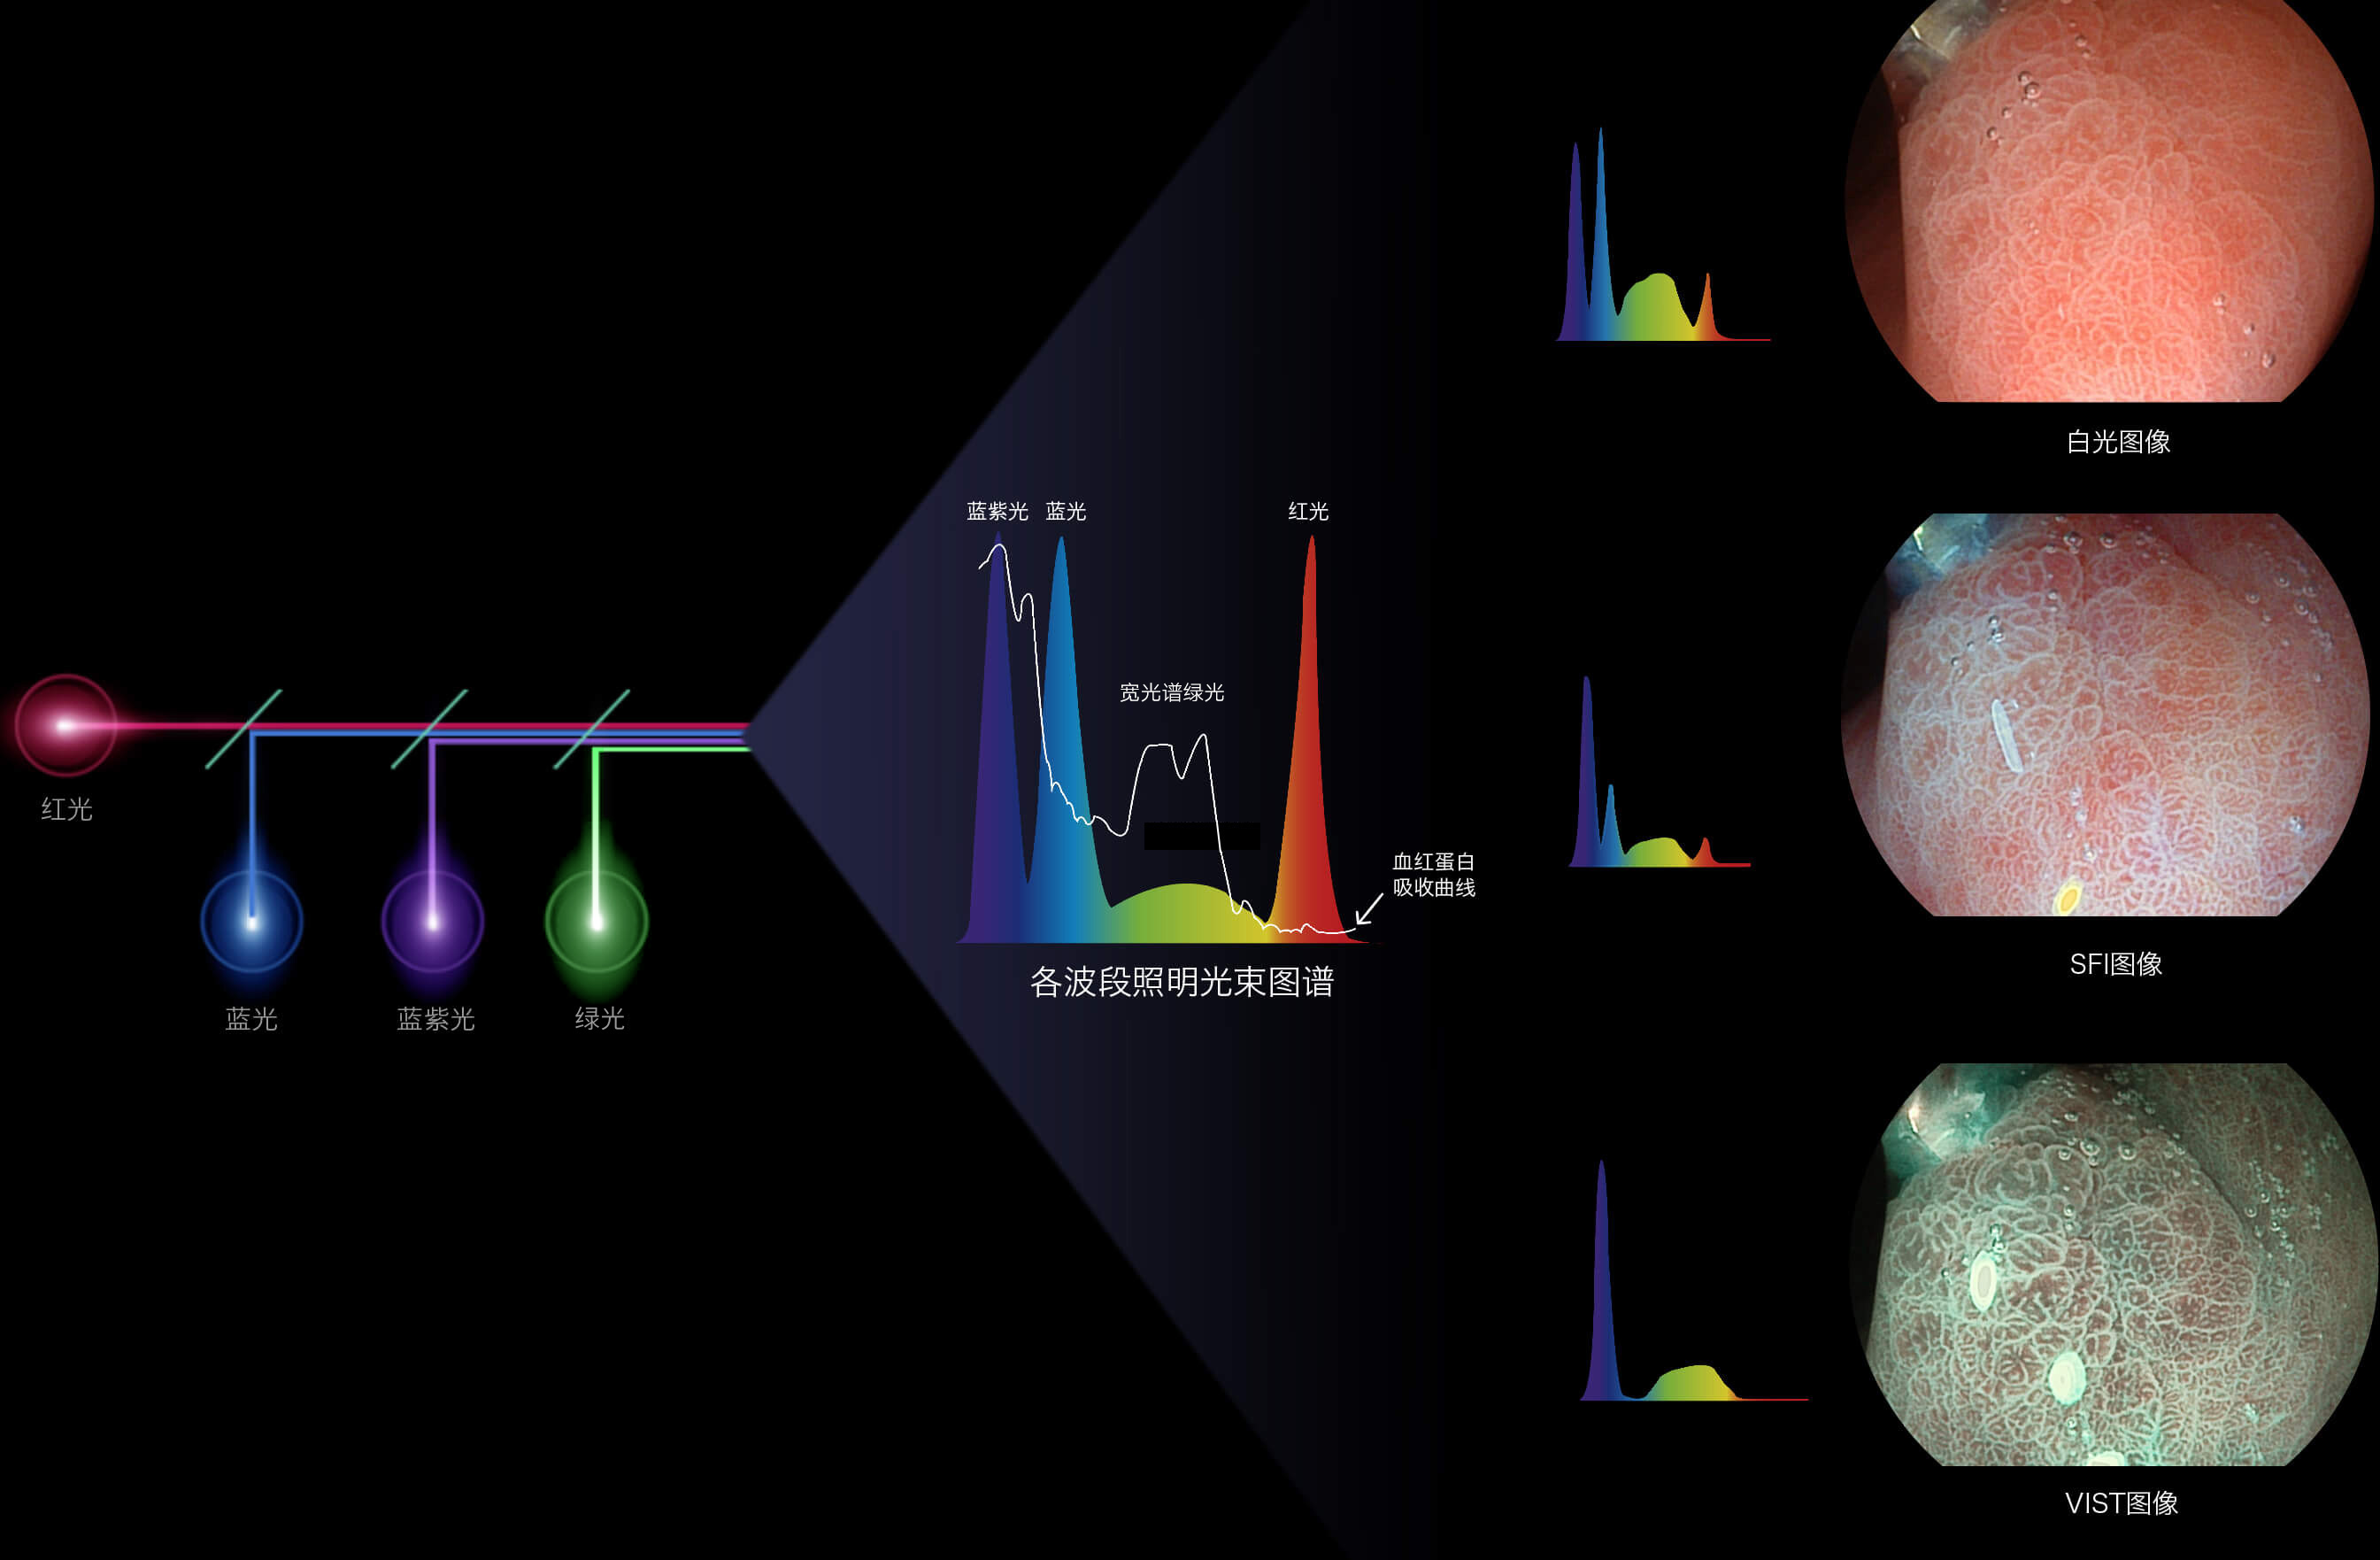

百老汇电子游戏官网新开发的内镜染色技术,主要是基于多波长LED 光源的开发,VLS-55Q 四波长LED 光源是由四个不同颜色的LED光按照相应照明模式所规定的特定发光比例进行合束后形成,合束后形成的照明光的光谱由红光、绿光、蓝光及蓝紫光这四个不同的波段范围构成。具有更高光谱自由度,通过光谱比例的控制,实现了聚谱成像技术,英文全称为“Spectral Focused Imaging, SFI”,缩写为“SFI”和光电复合染色成像技术,英文全称为“Versatile Intelligent Staining Technology, VIST”,缩写为“VIST”。